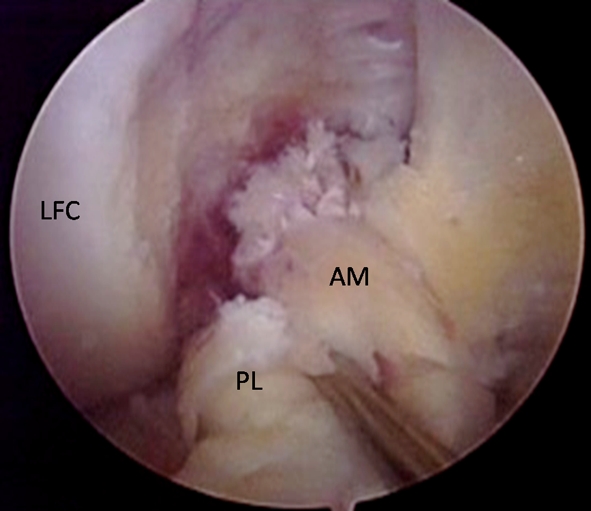

The most important finding of the present study was that the most common graft re-rupture pattern in ACL revision cases following previous single-bundle reconstruction was elongation of the graft, accounting for 58% of all revisions. This is significantly different from the most frequent rupture pattern seen in the native ACL, as reported by Zantop et al. [17], which is proximal rupture of both the anteromedial (AM) and posterolateral (PL) bundle (Fig. 6).

Fig. 6.

Arthroscopic anteromedial portal view of the right knee in 90° of flexion displaying the most frequent rupture pattern of the native ACL. Both the AM and PL bundle are ruptured proximally. When compared to the most common rupture pattern in revision surgery (Fig. 2), it clearly looks different. AM anteromedial, PL posterolateral, LFC lateral femoral condyle